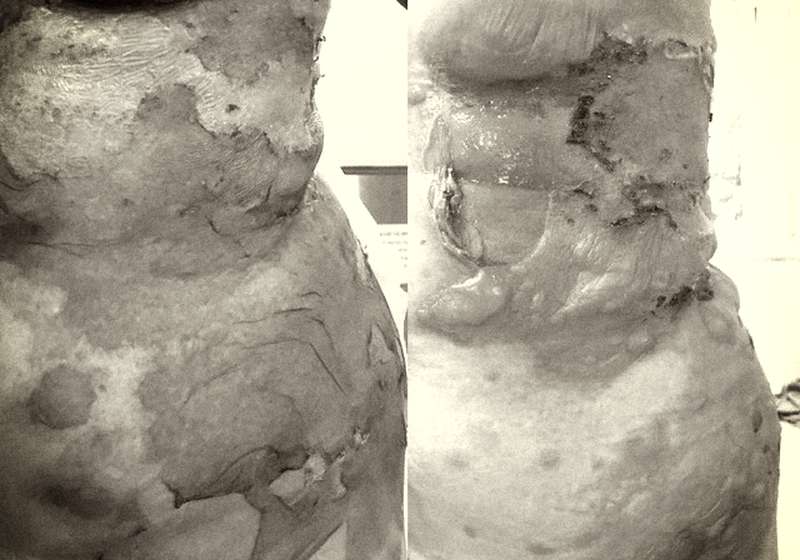

Bệnh viện Hữu nghị Việt Tiệp (Hải Phòng) vừa tiếp nhận một ca bệnh vào viện trong tình trạng nổi dát đỏ, bọng nước, trợt loét da chảy dịch ở ngực, bụng, lưng, bẹn trái.

Khoảng 4 ngày trước khi vào viện, vùng da đỏ phồng rộp lên thành những bọng nước lớn, dễ dập vỡ gây trợt loét da, chảy dịch ướt, ngứa, đau rát như bị bỏng, người bệnh mệt mỏi, ăn uống kém.

Tại bệnh viện, sau khi thăm khám, người bệnh được chẩn đoán: Viêm da tiếp xúc bội nhiễm.

Sau 8 ngày điều trị tích cực bằng các phương pháp toàn thân và chăm sóc tổn thương tại chỗ hàng ngày tại Khoa Da liễu, người bệnh tiến triển tốt, không xuất hiện tổn thương mới, tổn thương cũ thâm lại, trợt loét da khô hơn, bọng nước xẹp hết, ngứa rát giảm nhiều.